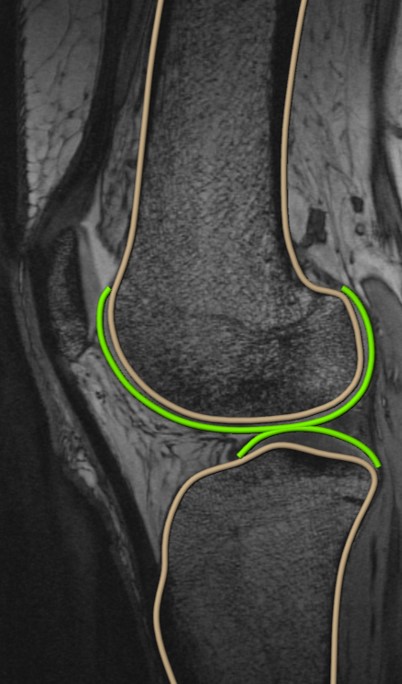

The gut microbiome is composed of diverse microbial ecosystems that exist in the gastrointestinal tract that have endocrine and immunological functions. We have recently established that dysbiosis, a shift from a “normal” gut microbiome, is associated with musculoskeletal disease, particularly osteoarthritis. Our lab’s work to establish a link between gut flora and osteoarthritis has uncovered the potential to target the gut microbiome to address joint degenerative disease. Currently, we are pursuing a deep study of the gut-joint axis, and in the process, we have developed strategies with preclinical efficacy in sculpting the microbial community in a manner that delays joint degeneration. We are currently testing one such strategy in symptomatic early-stage osteoarthritis in a human clinical trial.

Role of the gut microbiome in osteoarthritis